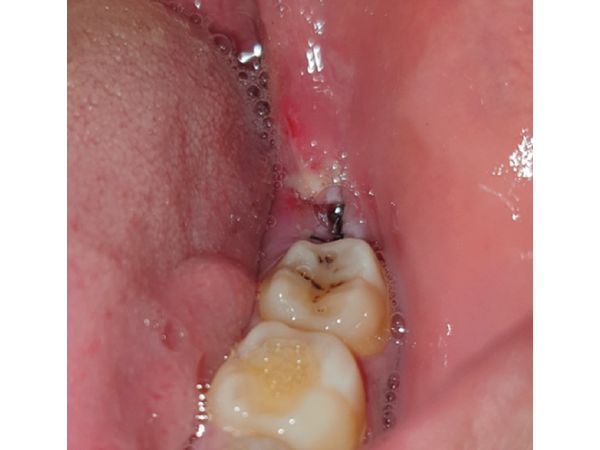

Через семь дней после удаления пациент пришёл на осмотр. Жалоб у него не было, рана заживала вторичным натяжением и без осложнений, динамика была положительной. В это же посещение сняли швы, лунку обработали физиологическим раствором (0,09%-м раствором Натрия хлорида).

На контрольном осмотре через 14 дней было видно, что десна зажила, признаков воспаления не было.